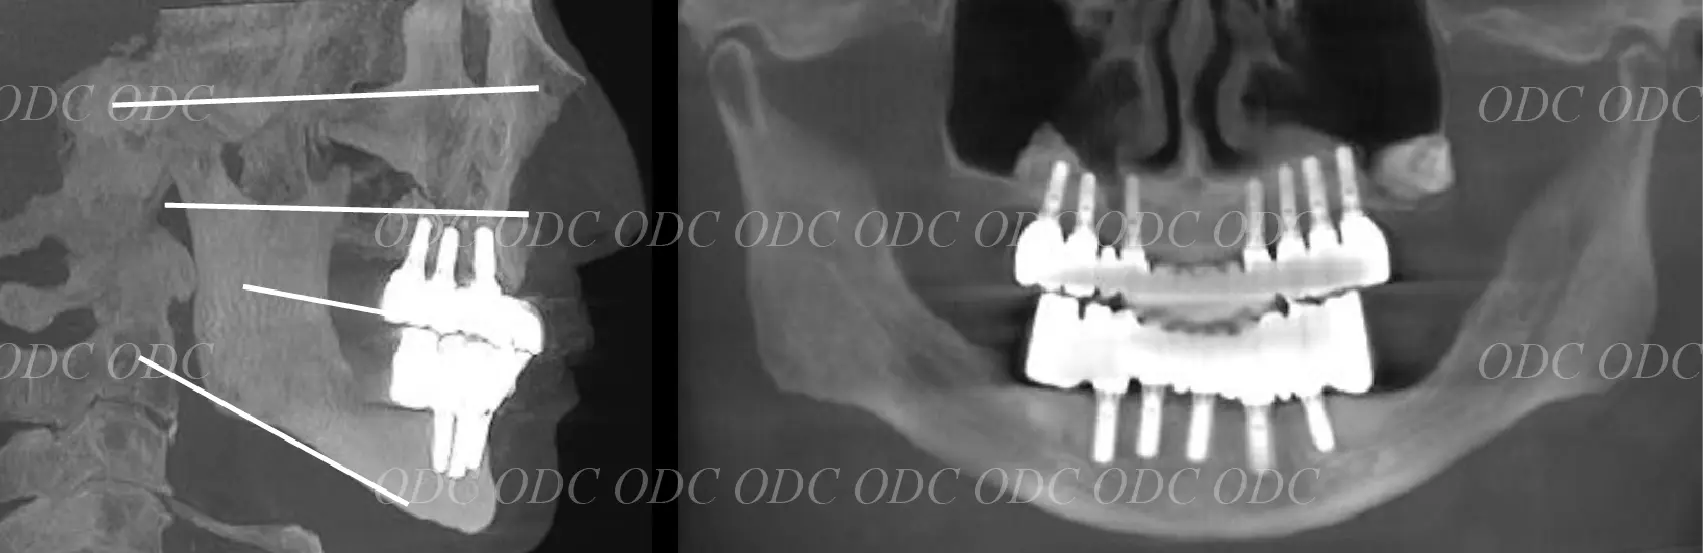

即時荷重症例

2006年、インプラント埋入後。

約1週間後、技工士さんに作成していただいた仮歯を装着。

2006年、手術後約3ヶ月。

インプラントの骨結合を確認後、インプラント上部構造を装着。

2006年、上部構造は第2世代CADCAMにより作成されたチタンフレームに人工歯を装着。

2006年(治療終了時)、女性、当時68歳。

口腔内及び口元のレントゲン。

2011年(写真左、5年経過)、2016年(写真中央、10年経過)、2024年(写真右、18年経過)。 2024年、約18年使用した上部構造が摩耗し、審美的な問題により再製を希望された。

2024年(上部構造再作成)、現在86歳でとてもお元気です。

インプラント体は20年弱経過しておりますが全く問題ありません。